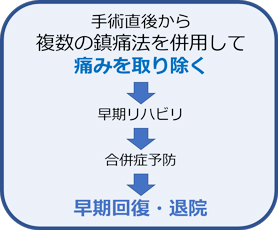

当チームでは「術後の痛みを十分に取り除くことは患者さまの権利」と考えています。そのため、手術のきずを小さくするだけでなく、手術直後から複数の鎮痛法を併用することで、患者さまから好評を得ています。また術後の痛みを積極的に取り除くことで、早期のリハビリが可能となり、早期回復につながっていると考えています。